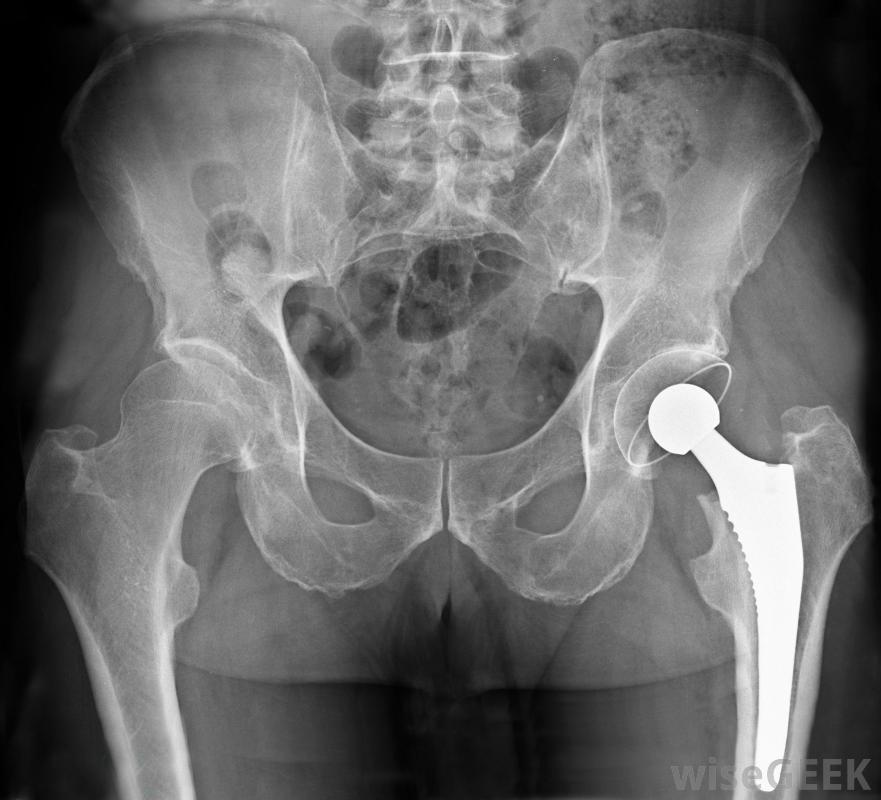

髖關節撞擊,也稱為股骨髖臼撞擊,或FAI,發生在移動髖關節時引起過多的摩擦或摩擦。這通常會導致腹股溝疼痛和關節活動困難,有時會導致關節炎。這些癥狀在疾病的早期階段通常不明顯,所以FAI通常多年未被診斷,當它出現時,它可能被分為兩種形式:凸輪和鉗子。這種撞擊可能是先天性的,或是在出生時出現的,也可能是隨著時間的推移而發展的,通常是由于遺傳傾向和環境的綜合作用髖關節撞擊嚴重時可采用髖關節置換術治療股骨和髖臼。股骨是從膝蓋到臀部的大骨頭,髖臼是骨盆向內彎曲的一部分。股骨的球形端與髖臼的窩狀形狀相吻合,使腿能夠旋轉運動。在健康的關節中,骨骼在在股骨和骨盆之間起緩沖作用的滑膜液和軟骨。但是,如果其中一塊骨頭變形,就會引起摩擦、軟骨破壞和疼痛MRI掃描可用于診斷股骨髖臼撞擊當股骨頭的形狀不正確時,通常是由于骨頭上的損傷而造成的。這可能會導致向前運動時的不適,例如當把膝蓋放在胸前或騎自行車時。這種情況會導致髖臼受到不正常的力,并磨損髖臼軟骨。凸輪-髖部撞擊可因先天或發育原因而發生。創傷可導致骨骼畸形,或患者可能患有髖內翻、股骨頭骨骺滑脫(SCFE)或缺血性壞死(AVN)。

酒精中毒可能導致缺血性壞死。a醫生可以使用多種方法來診斷FAI。醫生會查看患者的病史,傾聽癥狀,進行身體檢查,并通常進行X光檢查。還可以要求MRI(磁共振成像)排除其他導致僵硬和疼痛的原因。如果患者被診斷為髖關節撞擊,醫生可能會嘗試手術矯正關節的形狀和方向。但是,如果軟骨損傷嚴重,髖關節置換術可能是最好的選擇。